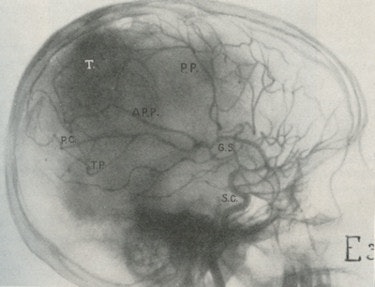

After these techniques failed, he tried using intra-arterial injections using an iodide salt. Moniz chose iodine because of its higher atomic weight compared with bromine. After many difficulties, he was successful using a 25% solution of sodium iodide with bilateral carotid artery cut downs. His successful patient, on 28 June 1927, was the ninth in his series, a young man with a pituitary tumor. In 1932, Moniz showed the head positioned for angiography (fig. 3) and angiogram (fig. 4) showing a tumor "T."

Fig. 3: Positioning for cerebral angiography (1932).